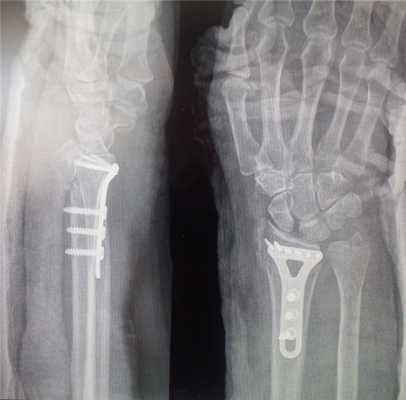

После операции:

После операции